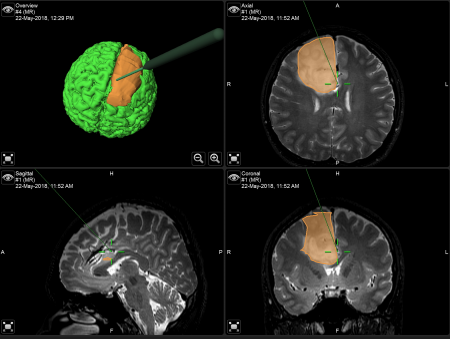

รศ.นพ.กฤษณพันธ์ บุณยะรัตเวช ศัลยแพทย์เฉพาะทางด้านประสาทศัลยศาสตร์ โรงพยาบาลจุฬาลงกรณ์ สภากาชาดไทย อธิบายถึงความแตกต่างของการผ่าตัดสมองแบบผู้ป่วยตื่น(Awake Craniotomy) และการผ่าตัดสมองโดยทั่วไปว่า การผ่าตัดสมองโดยทั่วไปผู้ป่วยจะไม่รู้สึกตัวจนกระทั่งการผ่าตัดเสร็จสิ้นทุกกระบวนการ แต่การผ่าตัดสมองแบบผู้ป่วยตื่นนั้น ผู้ป่วยจะถูกปลุกให้ตื่นขึ้นมาในช่วงหนึ่งของการผ่าตัดเพื่อให้แพทย์สามารถตรวจสอบการตอบสนองของผู้ป่วย เช่น การพูด การขยับแขนหรือขา การเปิด-ปิดตา และการรับรู้ความรู้สึก ฯลฯ เพื่อให้แน่ใจว่าการผ่าตัดสมองนั้นไม่ได้กระทบสมองส่วนอื่นๆที่สำคัญของผู้ป่วย การผ่าตัดรูปแบบนี้เป็นเทคนิคการผ่าตัดที่ใช้สำหรับผ่าตัดเนื้องอกในสมองหรือการผ่าตัดฝังเครื่องกระตุ้นสมอง ซึ่งบริเวณสมองส่วนที่ผ่าตัดนั้นจะอยู่ใกลกับสมองส่วนทีมี่ความสำคัญ เช่น เป็นสมองส่วนควบคุมการพูด การเคลื่อนไหวแขน ขา การกลอกตา การรับรู้ความรู้สึก เป็นต้น

หลังจากที่แพทย์อธิบายให้ผู้ป่วยเข้าใจถึงกระบวนการทดสอบแล้ว เมื่อถึงเวลาผ่าตัด วิสัญญีแพทย์จะให้ยานอนหลับและยาแก้ปวดแก่ผู้ป่วย ซึ่งในช่วงที่ผู้ป่วยนอนหลับนั้นเป็นช่วงเวลาสำคัญที่วิสัญญีแพทย์จะต้องดูแลระบบหายใจและระบบไหลเวียนเลือดให้เกิดความปลอดภัย อาจต้องมีการใส่อุปกรณ์เปิดทางเดินหายใจเพื่อให้ผู้ป่วยสามารถหายใจเข้า–ออกได้อย่างสะดวก ฉีดยาชาที่บริเวณหนังศีรษะเพื่อลดความเจ็บปวดขณะตื่น ศัลยแพทย์จะใส่หมุดตรึงศีรษะเพื่อให้ผู้ป่วยอยู่ในตำแหน่งที่สามารถผ่าตัดได้อย่างสะดวก และใส่สายสวนปัสสาวะเพราะการผ่าตัดอาจยาวนานและอาจต้องให้ยาขับปัสสาวะเพื่อลดอาการสมองบวม จากนั้นศัลยแพทย์จึงเริ่มทำการผ่าตัดสมอง

รศ.นพ.กฤษณพันธ์ กล่าวสรุปถึงประโยชน์ของการผ่าตัดสมองแบบผู้ป่วยตื่น (Awake Craniotomy) ว่า เป็นการผ่าตัดที่มีประโยชน์อย่างยิ่งเนื่องจากการผ่าตัดด้วยวิธีนี้ช่วยให้ศัลยแพทย์สามารถผ่าตัดรักษาในกลุ่มโรคที่มีอาการอยู่ใกล้กับสมองส่วนที่มีความสำคัญได้เป็นอย่างดี อีกทั้งยังเป็นการรักษาที่มีประสิทธิภาพมาก เพราะในระหว่างการผ่าตัด แพทย์สามารถให้การรักษาผู้ป่วยได้อย่างเต็มที่ที่สุดและเห็นการตอบสนองของผู้ป่วยได้อย่างชัดเจน นอกจากนี้การผ่าตัดสมองแบบผู้ป่วยตื่นจะสำเร็จลุล่วงไม่ได้เลย หากขาดการประสานงานที่ลงตัวระหว่างศัลยแพทย์และวิสัญญีแพทย์ ที่ต้องทำให้ผู้ป่วยหลับและตื่นขึ้นมาเพื่อทำการทดสอบการตอบสนองต่างๆ ให้เป็นไปอย่างราบรื่นที่สุด ที่ผ่านมาโรงพยาบาลจุฬาลงกรณ์สามารถให้การผ่าตัดรักษาผู้ป่วยด้วยวิธีการนี้สำเร็จไปแล้วกว่า 80 ราย ซึ่งในอนาคตทีมแพทย์โรงพยาบาลจุฬาลงกรณ์จะพัฒนาการผ่าตัดสมองแบบผู้ป่วยตื่นให้มีประสิทธิภาพมากยิ่งขึ้นเพื่อช่วยให้ผู้ป่วยกลับมามีคุณภาพชีวิตที่ดีขึ้นได้ต่อไป